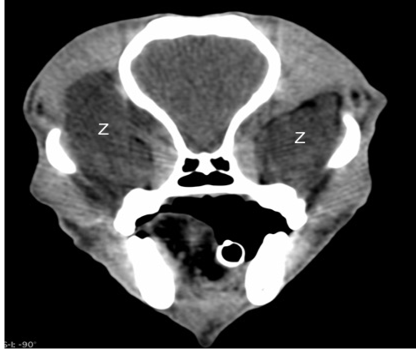

Figure 2

Pre-contrast computed tomographic image in a soft tissue window showing bilateral retrobulbar masses (Z). Both masses are hypodense and poorly defined and larger on the right (left side of image).